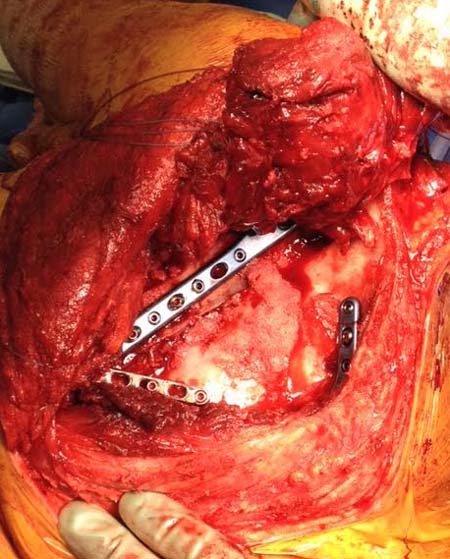

Здесь пример, стандартные снимки: плечо и лопатка прямой снимок,

аксиллярный и косой снимки (Y-view) и фиксация пластинами по краям, где

имеется более твердая кость. Специальные пластины, хотя любая 2.7 или

3.5 мм тубулярная пластина подойдут для фиксации перелома. Риск операции

- это повреждение нерва во время доступа и ре-фиксация ротаторной

манжетки если потребуется широкий доступ!